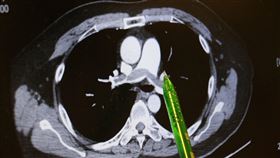

壯男洗澡突肺栓塞休克 3步搶命奇蹟生還

台中一名34歲林先生,身體向來健康,還有一周兩次打籃...

產婦突「咳一聲」⋯20多人緊張搶救6小時

正在分娩的產婦突然咳嗽一聲,這在很多人眼裡並不是什麽...

男不菸不酒 上班久坐、躺沙發誘發肺栓塞

六旬男子走樓梯突然感覺呼吸急喘、嘴唇發紫且冒冷汗,緊...